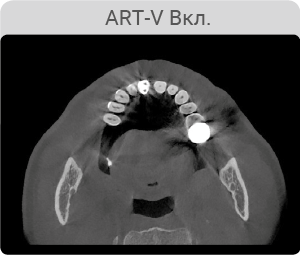

Технология ART-V - уменьшение артефактов

Артефакты от металлов мешают визуализации и естественным образом снижают достоверность диагностики. Четкие изображения дают вам меньше поводов волноваться и больше доверия к результатам диагностики при планировании имплантации. А также вам не составит труда планирование хирургического шаблона.

*ART-V новое название алгоритма коррекции артефактов от VATECH.